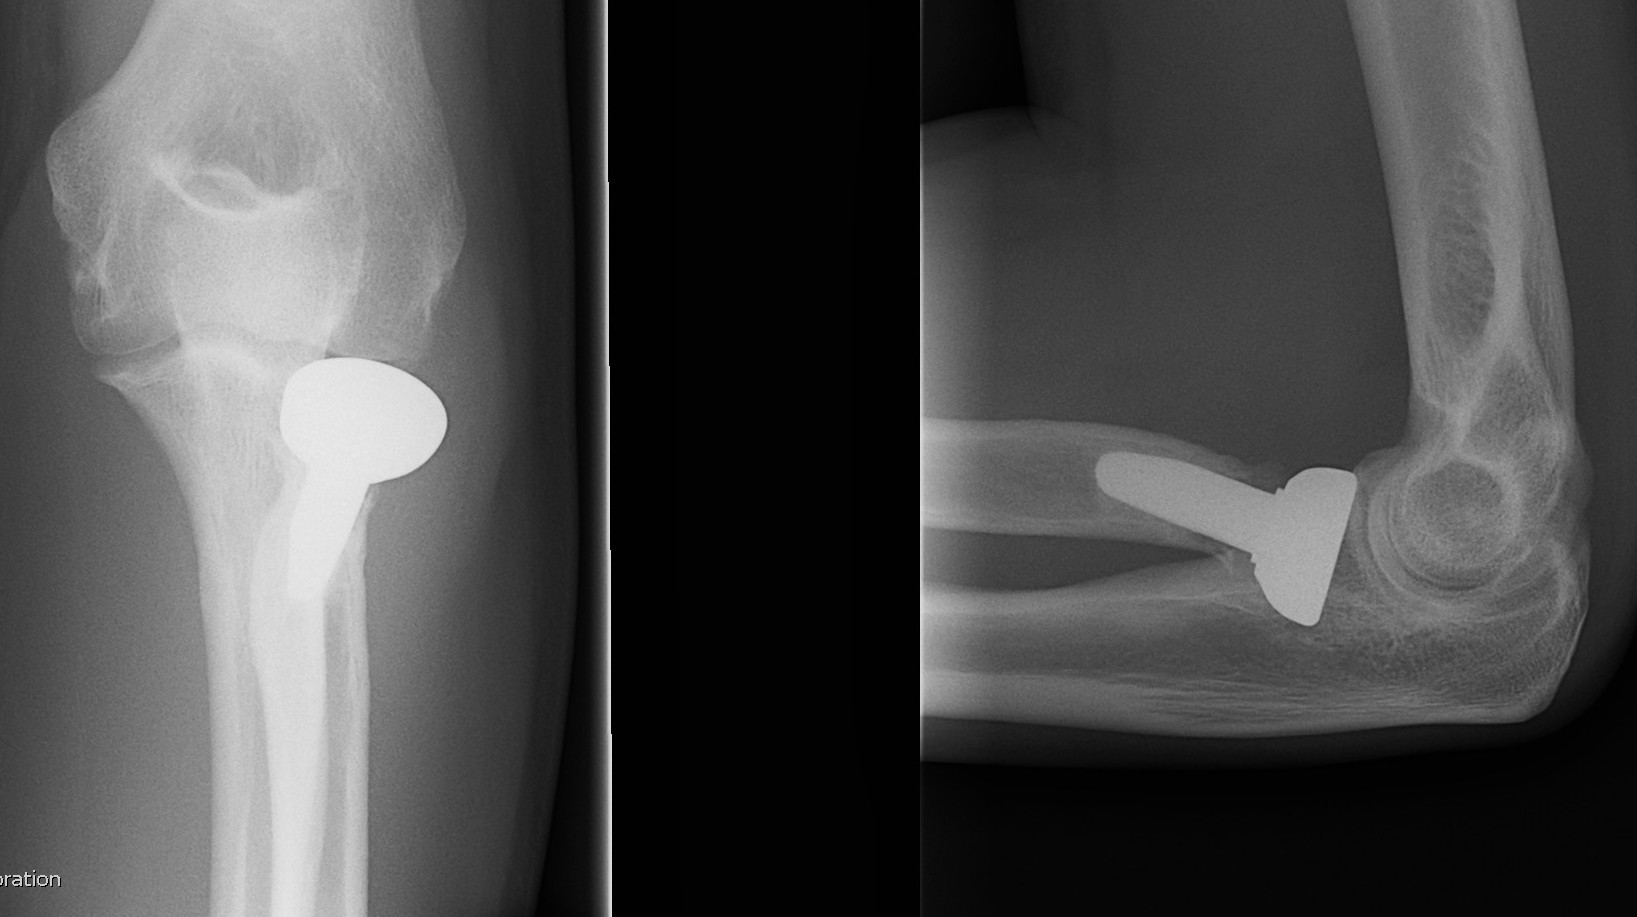

![]() |

Overstuffing

| Lesser sigmoid notch | Symmetry of ulnohumeral joint |

|---|---|

|

Radial head shoulder articulate with lesser notch

Ensure no gapping of lateral ulnohumeral joint |

- cadaveric study

- increased medial ulno-humeral joint line gapping with overlengthening of 6 or 8 mm

- increased lateral ulno-humeral joint line gapping with overlengthening of 2 mm